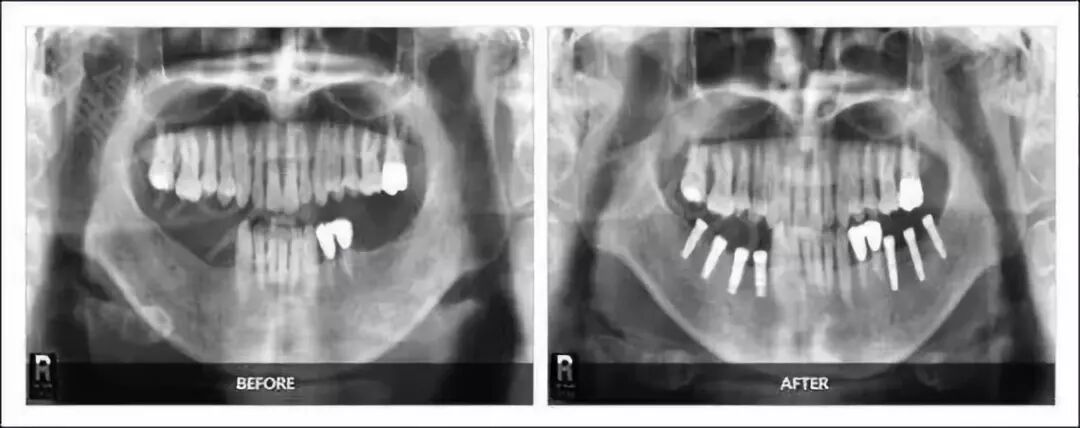

申领要求:申领市民需提供术前术后口腔全景片,如下图所示:(主办方提供当场免费拍片服务)

术前术后口腔全景片例图